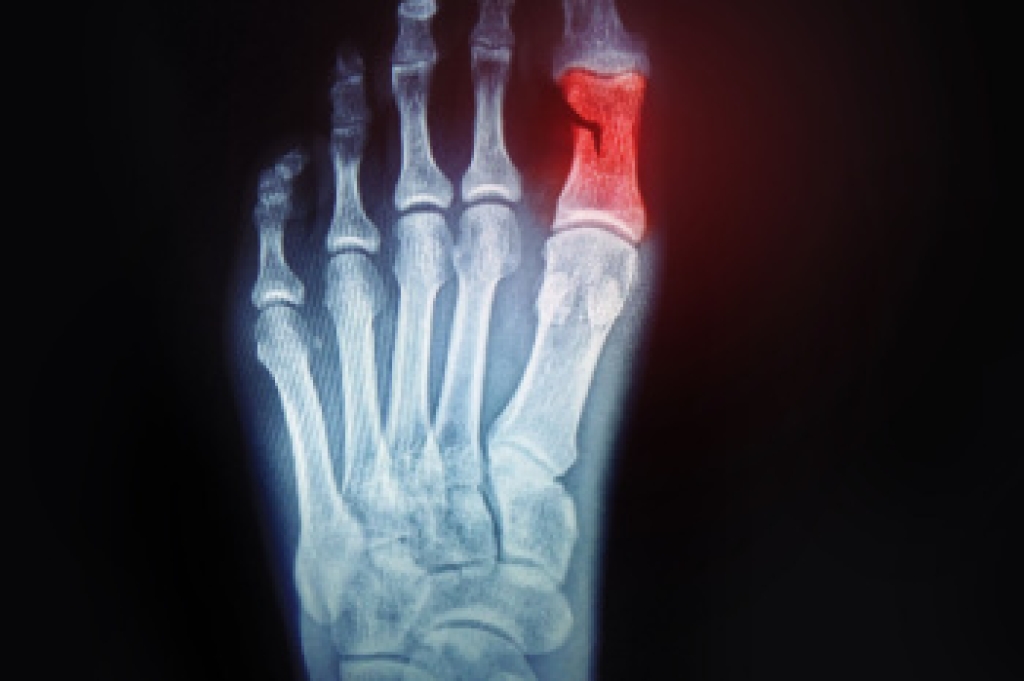

Diagnosis

Diagnosis of cuboid syndrome is often difficult, and it is often misdiagnosed. X-rays, MRIs and CT scans often fail to properly show the cuboid subluxation. Although there isn’t a specific test used to diagnose cuboid syndrome, your podiatrist will usually check if pain is felt while pressing firmly on the cuboid bone of your foot.